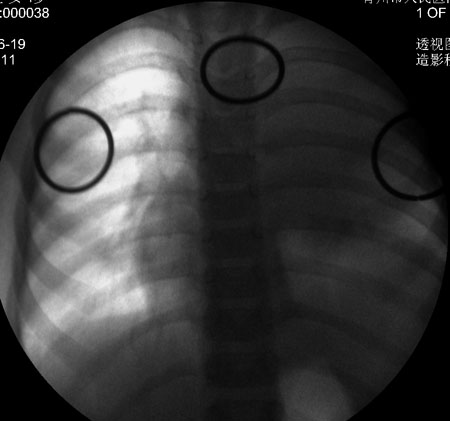

透视采集图像!

此病人是我接手的,发热、咳嗽来做胸透,透视见左侧肺野大部密实,纵隔、心影明显左移,呼吸示纵隔摆动、膈肌矛盾运动(透视下采集了几幅图片),左肺动度明显减弱。询问病人家长,没有吃花生米等呛咳史。由于其影像特征明显,当时诊断:考虑左侧支气管异物并阻塞性肺不张、肺炎。